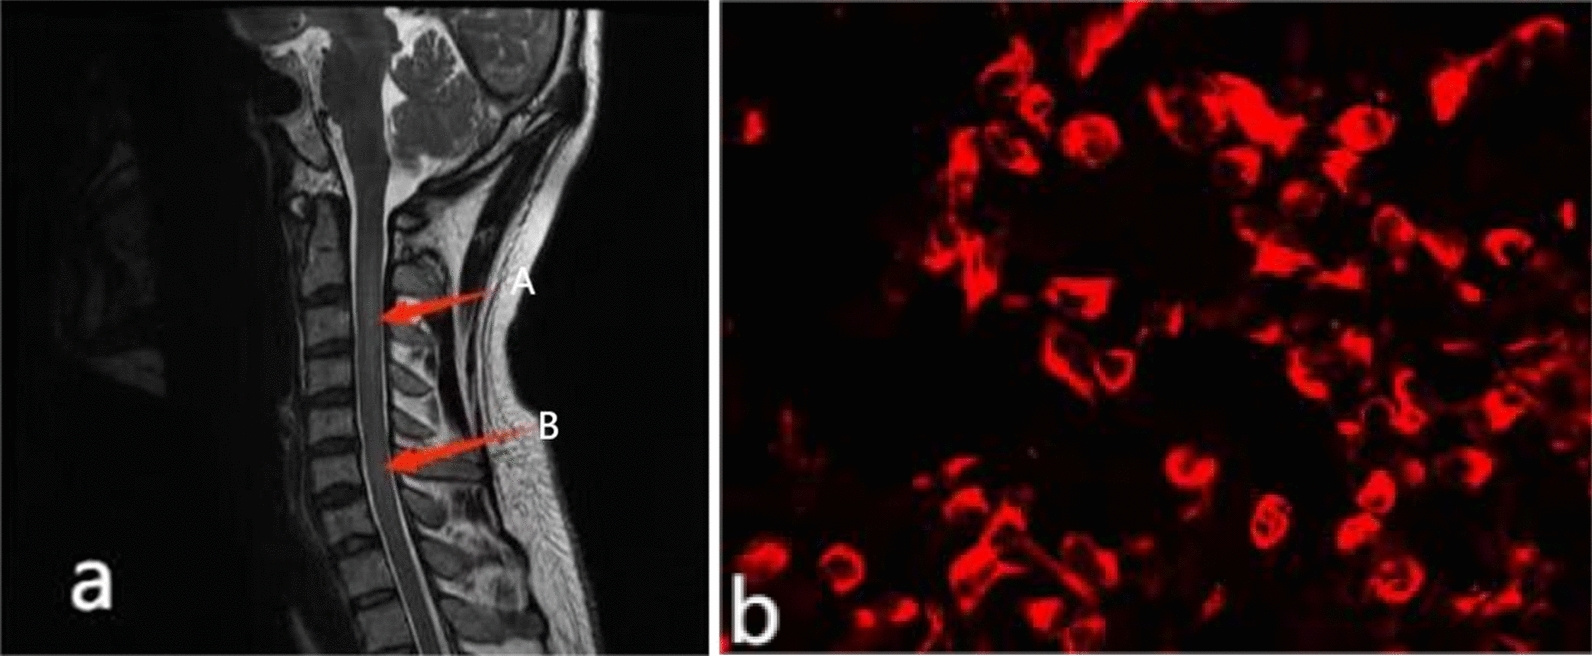

This case report describes two patients who were initially diagnosed with tuberculous meningitis based on a combination of subacute neurological symptoms, cerebrospinal fluid (CSF) inflammatory findings, and neuroimaging features consistent with infectious meningitis . Both individuals presented with clinical features highly suggestive of TBM, including headache, fever, and progressive neurological deficits, alongside CSF profiles demonstrating lymphocytic pleocytosis, markedly elevated protein, and reduced glucose or chloride levels. Magnetic resonance imaging further supported the presumed diagnosis, revealing diffuse leptomeningeal enhancement. In one case, a positive T-SPOT test reinforced diagnostic anchoring toward tuberculosis. However, despite appropriate antimicrobial and antituberculous therapy, both patients exhibited clinical worsening or failed to improve, prompting reconsideration of the initial diagnosis.

Subsequent evaluation revealed the presence of glial fibrillary acidic protein immunoglobulin G (GFAP-IgG) antibodies in the CSF and/or serum, leading to the diagnosis of autoimmune GFAP astrocytopathy. Clinically, the cases highlight the heterogeneity of this condition: one patient developed prominent cerebellar ataxia with meningoencephalomyelitis and optic involvement, while the other exhibited systemic symptoms including fever and tremor, along with autonomic dysfunction such as urinary retention. Notably, both patients developed hyponatremia during the disease course, an underrecognized but reported feature of GFAP astrocytopathy. Radiologically, although leptomeningeal enhancement overlapped with TBM, the broader pattern of central nervous system involvement—including spinal cord abnormalities—supported an inflammatory autoimmune process.